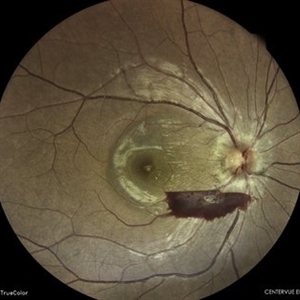

Old Supero-Temporal Branch Retinal Vein Occlusion with Macular Hole Right Eye Fundus

Fundus photograph of a 36-year-old female presented with supero-temporal branch retinal vein occlusion with macular hole in right eye.

Photographer: Dr. Akansha Sharma-Retina Foundation

Condition/keywords: branch retinal vein occlusion (BRVO), macular hole